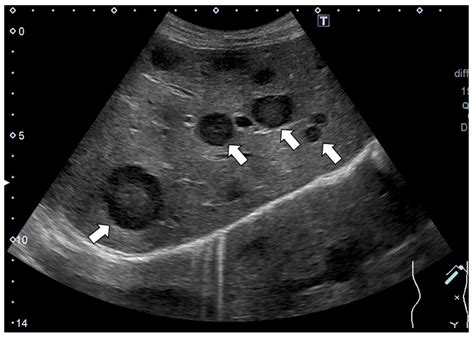

• Liver Cysts: These are fluid-filled sacs within the liver. They are generally harmless unless they grow large enough to cause discomfort by pressing on surrounding organs.

The vast majority of findings categorized as a lesion on liver are benign. These are typically growths that do not cause significant symptoms and are often discovered by chance. Common types include:

Common Types of Benign Liver Lesions